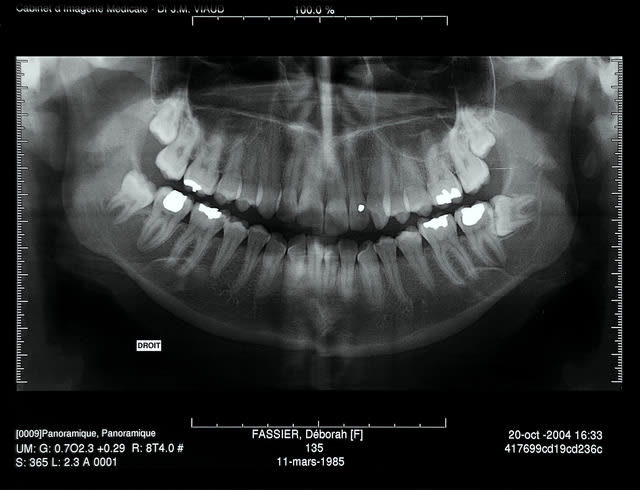

Extraction en 2004

La patiente ne revient pas après, pano demandé par un confrère en 2007 mais la patiente ne retourne pas le voir

Cadeau cette année elle vient pour faire finir 47

Pano demandé